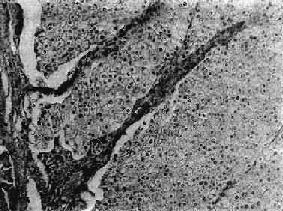

镜下,癌细胞形态和排列多样,多数癌细胞体积较大,呈多角形,轮廓清楚,胞浆清亮透明;细胞核小而深染,位于细胞中央或边缘。癌细胞常排列成片状(图12-27)、条索状、腺泡状或管状,很像肾小管(图12-28)。以这种形态结构为主的称为透明细胞癌。这种类型在肾细胞癌中最为多见。有些肾细胞癌由颗粒细胞组成。癌细胞体积较大,呈立方形或多角形,胞浆呈伊红色细颗粒状;核圆形,多位于细胞中央。分化较好的癌细胞比较规则,排列成腺状或片状;分化不好的癌细胞大小形状不规则,胞浆深染,核大并有多数核分裂像,有时并有癌巨细胞形成。高度未分化的癌细胞呈梭形或不规则形,似肉瘤样,称为未分化癌。有时癌组织中有大量乳头状结构,这种结构可见于透明细胞癌的某些区域,也可为肾细胞癌的主要成分,称为乳头状腺癌。有时其间并有囊肿形成则称为乳头状囊腺癌。以上各种类型之间常有过渡形式。在大多数肾癌中,几种类型常同时并存,而以某一类型为主。癌组织的间质很少,但血管丰富,有些区域纤维组织可增多,常有出血、坏死和钙化。

图12-27 肾透明细胞癌

癌细胞呈多角形或立方形,轮廓清楚,胞浆透明,核居中,深染。癌细胞排列成片状,间质很少